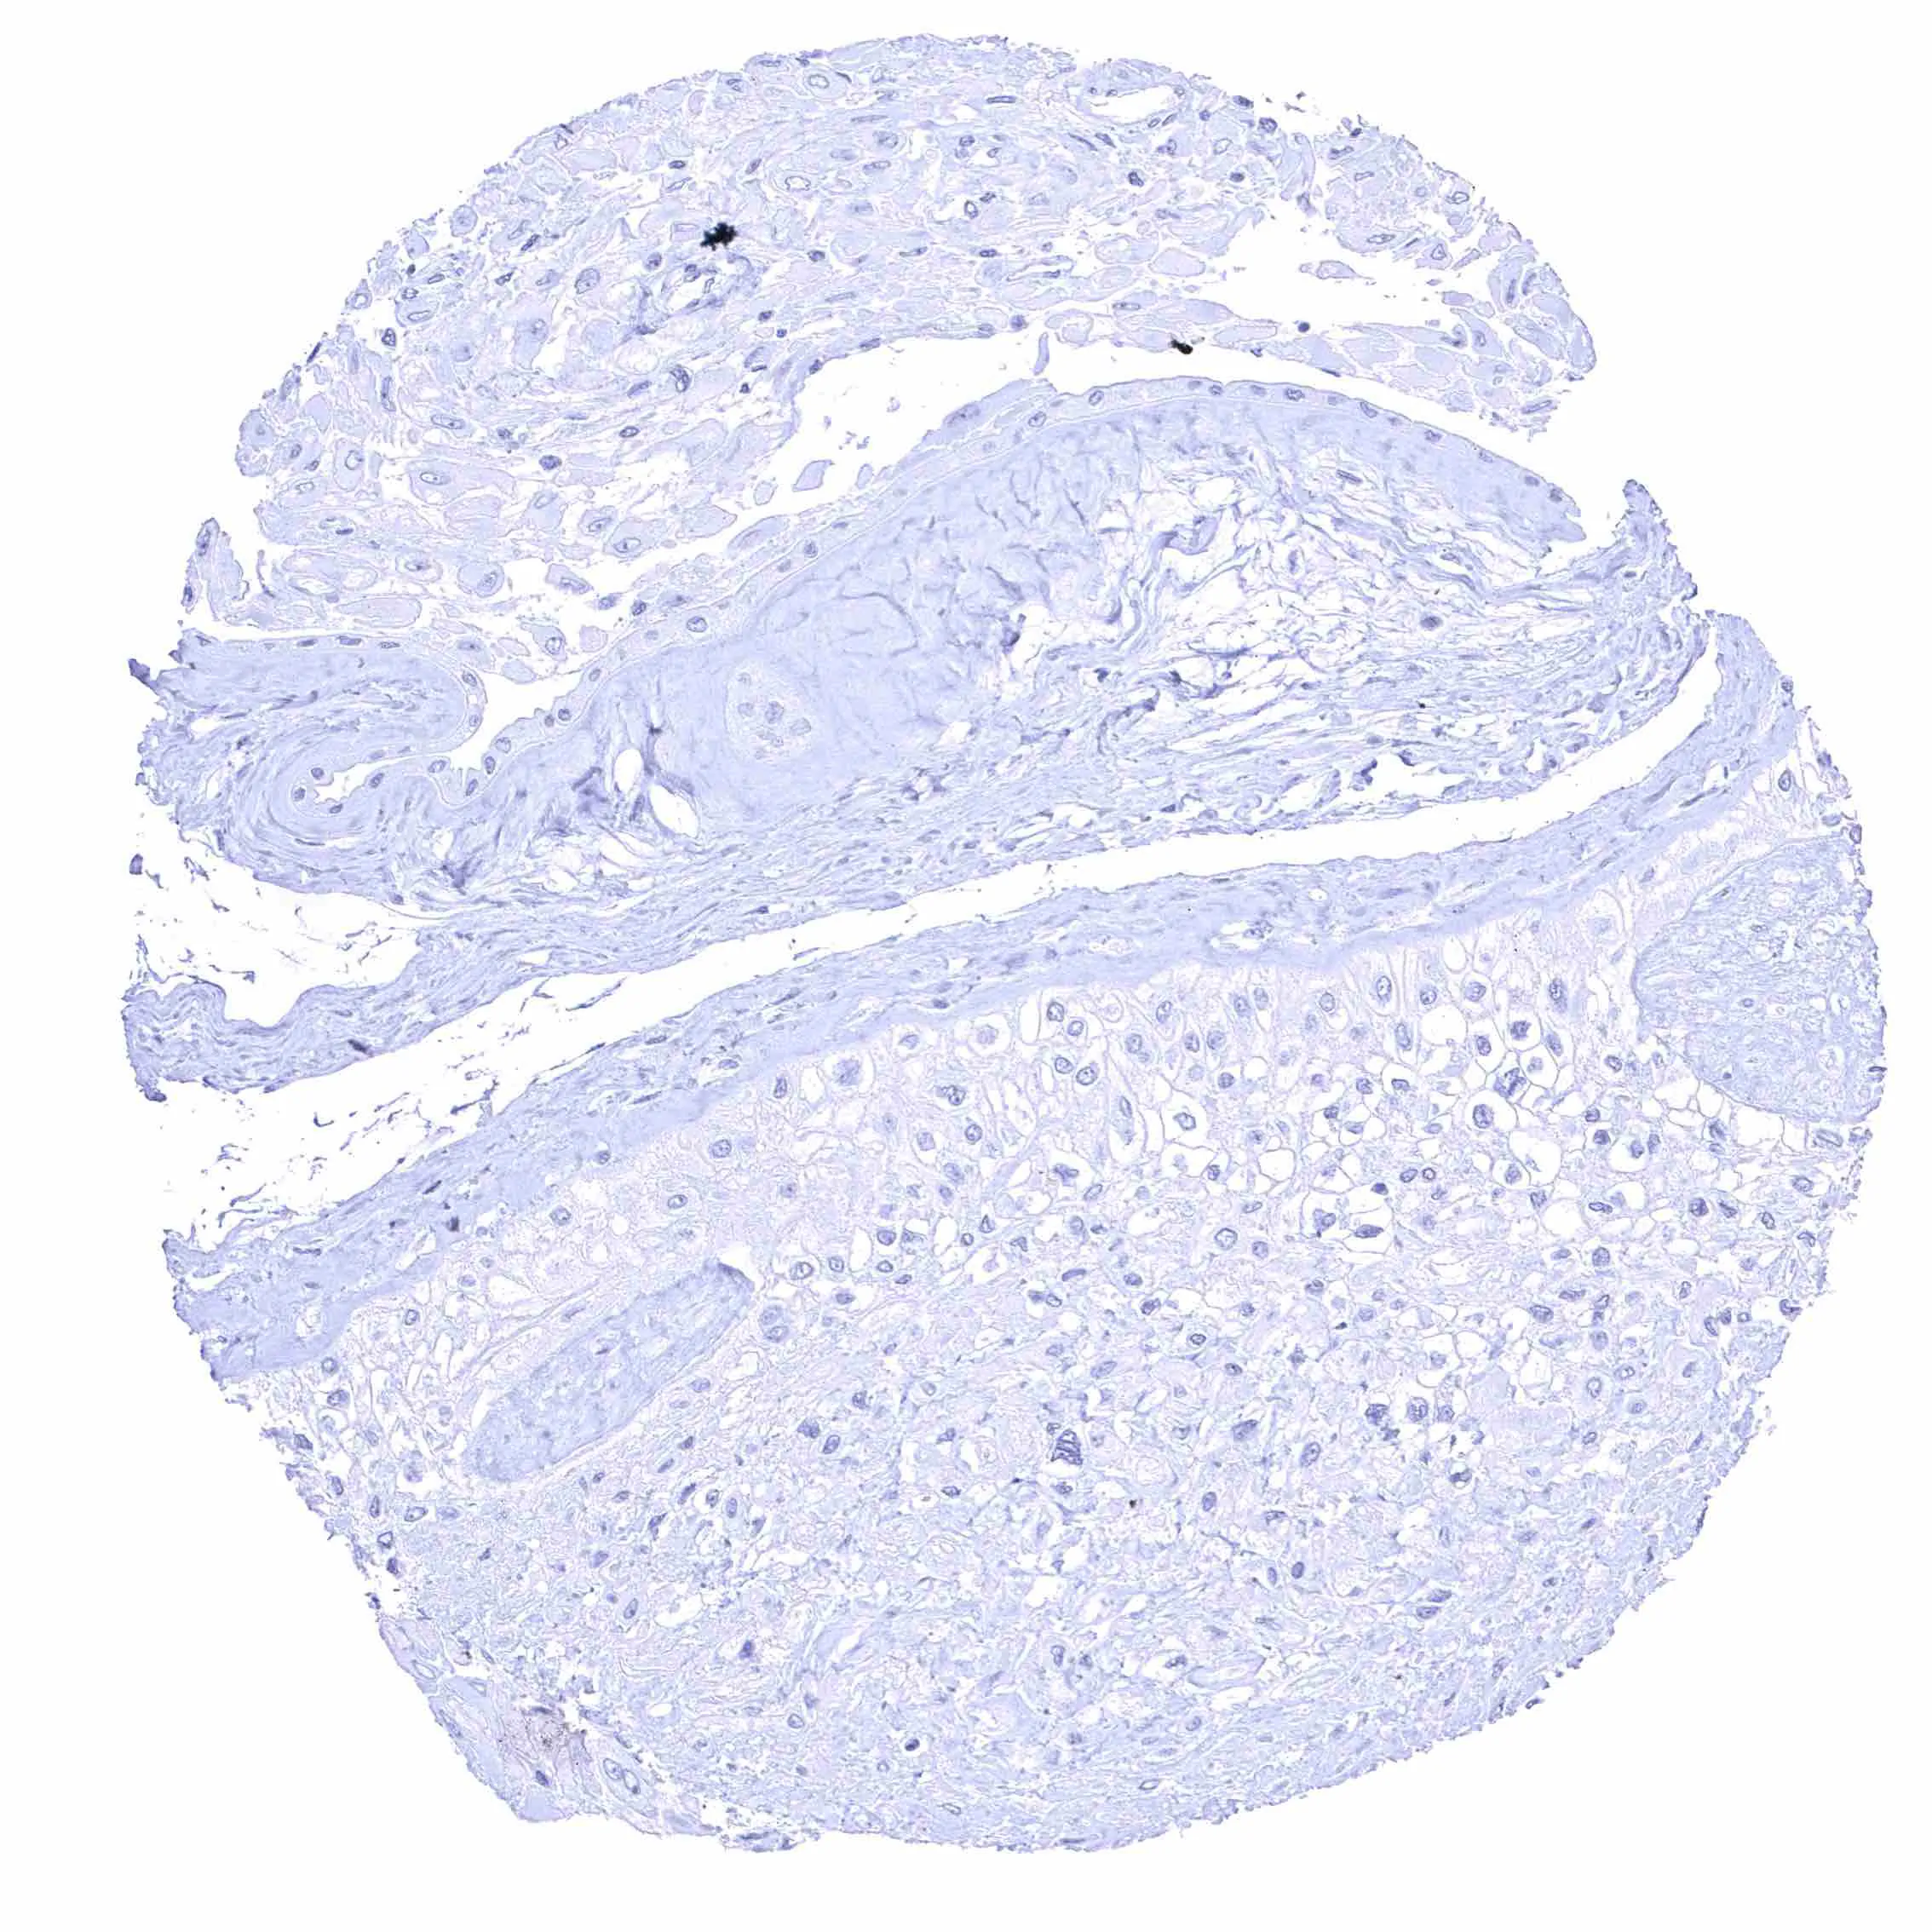

Uterus, ectocervix